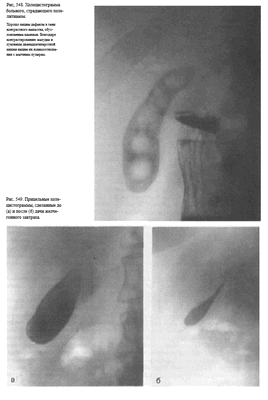

Холецистография — методика рентгенологического исследования желчного пузыря, основанная на способности печеночных клеток поглощать из крови некоторые йодсодержащие вещества и выделять их с желчью в желчный пузырь, который обладает способностью концентрировать свое содержимое. Показанием к холецистографии является подозрение на вляют путем однократного (за 14—15 ч) или фракционного (метод насыщения) приема внутрь ди- или трийодированных контрастных веществ (билитраст, билиграфин, йопагност, холевид) и последующей рентгенографии в положении больного стоя за экраном и лежа на животе.

Рекомендуется делать 4 снимка: два — в прямой передней проекции в положении больного стоя (один — без компрессии, второй — с компрессией), третий снимок также в положении больного стоя в левой косой проекции и последний — в положении больного лежа на спине. Первые три снимка обычно выполняют за экраном рентгеновского аппарата под контролем просвечивания, последний — на снимочном столе (рис. 546). Кассету размером 24X30 см устанавливают под правую половину живота с таким расчетом, чтобы центр ее находился на середине расстояния между нижними ребрами и гребнем правой подвздошной кости.

У здоровых людей на холецистограммах определяется интенсивная однородная тень желчного пузыря с четкими контурами (рис. 547).

При калькулезных холециститах тень пузыря менее интенсивна, в проекции пузыря определяются дефекты наполнения, образованные камнями(рис. 548).

Для оценки сократительной и эвакуационной функции желчного пузыря после выполнения снимков (при наличии на них отображения тени желчного пузыря) больному дают желчегонный завтрак (сырые желтки, сливочное масло, сорбит) и спустя 20 и 50 мин делают прицельные снимки (рис. 549).